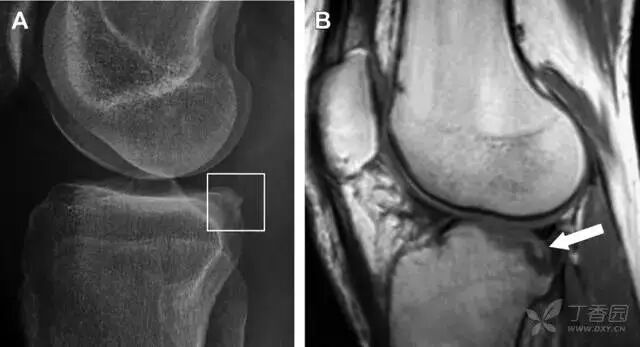

10胫骨后外侧碎片骨折

胫骨后外侧小片骨皮质的压缩性骨折,可能是旋转移位损伤的唯一证据(图 3)。这种骨折在常规膝关节平片很难发现,若怀疑存在骨折,行下肢内旋斜位片检查可诊断。

图 3 胫骨后外侧碎片骨折

A 正位片示胫骨后外侧处可见一压缩骨折的小碎片(方框)。这是胫骨撞击股骨外侧髁旋转移位时所致。B 另一位患者的 MRI 矢状位 T1 加权像示胫骨后外侧骨折碎片(箭头)。